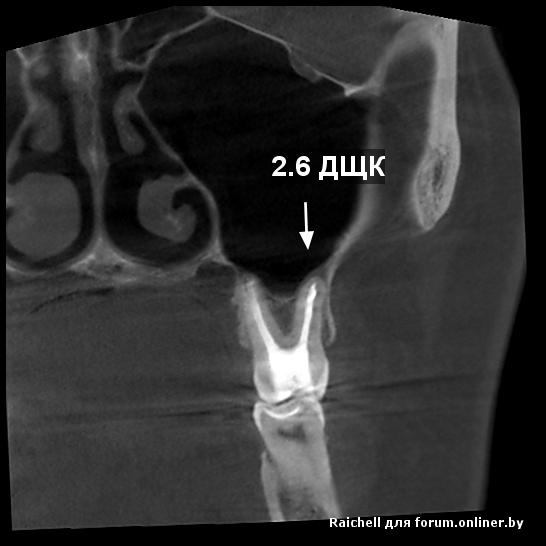

Во всех депульпированых зубах есть проблемы, плюс в пазухе слева от 25 зуба есть нюанс

inycik:Во всех депульпированых зубах есть проблемы, плюс в пазухе слева от 25 зуба есть нюанс

16,15 на удаление, потом синус и имплантация

Все зубы перелечила. это кт до лечения. Сейчас под временными коронками. Предлагают имплантацию 1.5,2.5 и 4.5 (убрать мост, т.к. 4.6 сильно разрушен). 1.5 удалить и сразу же имплант, но про наращивание не говорили.

А скажите, что в пазухе? Это как-то повлияет на имплантацию